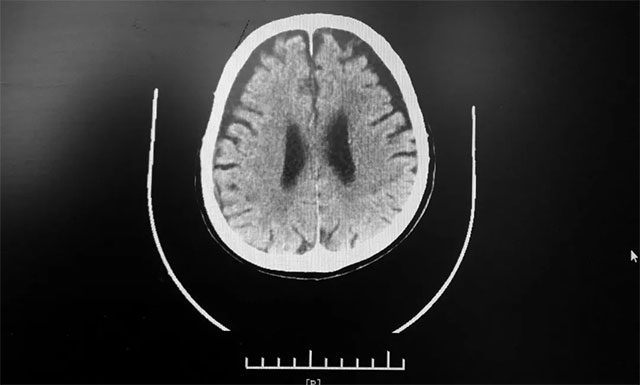

15:00 患者头部CT检查完成,影像科3分钟出报告,CT报告排除患者脑出血。根据影像学检查结果,并结合其有脑梗发病史,张琪主任判断患者为急性脑梗,发病时间为12:10分左右,还处于静脉溶栓治疗4.5小时的时间窗内,有溶栓治疗指征,可溶栓治疗,积极治疗血管有再通希望。

▲ 根据急诊CT影像结果,排除患者脑出血